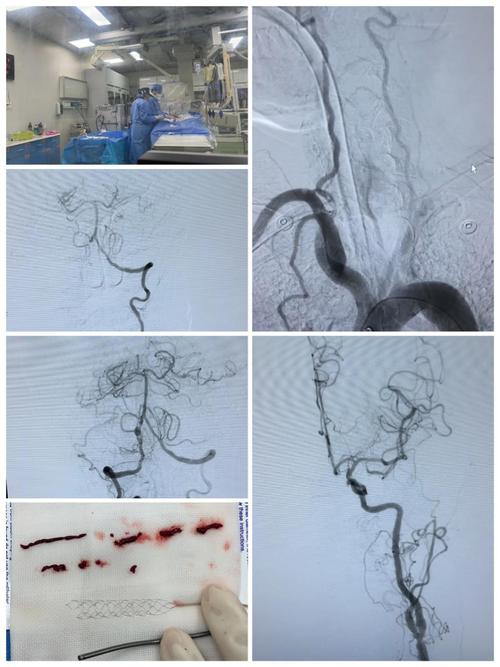

2023年3月1日,国家卒中中心建设管理平台根据相关技术开展、随访管理、培训、专业技术等对全国579家高级卒中中心进行评估并排名,济南市中心医院在全国高级卒中中心综合质控排名第32位,急性缺血性卒中血管内治疗介入再通技术全国综合质控排名第9位,全市排名第1位。

脑卒中已成为中国居民的首要死亡原因,具有高发病率、高致残率、高死亡率、高复发率等特点。早发现,早诊治是降低疾病风险,改善患者预后的有效手段。2023年1月,在全国各地饱受疫情肆虐的艰难时刻,济南市中心医院卒中中心仍坚持排除万难,保证绿色通道的畅通无阻;日接诊病人数量破百,单月静脉溶栓例数、取栓数量均在20例以上。极大的降低了急性缺血性卒中致死/致残率,减轻了家庭和社会的负担,最大限度缩短了患者血管再通的时间,做泉城百姓忠诚的脑血管守护者。

济南市中心医院卒中中心是济南市卒中中心,济南市首批国家卫生健康委脑卒中防治工程委员会批准的 “国家级高级卒中中心”,也是全国首批55家“高级卒中中心”之一。济南市中心医院高级卒中中心,坚持“365天24小时神经内、外科急诊医师值班,二线卒中医师听班,神经介入医师随时待命”的急救制度,逐步缩短脑卒中患者DNT(就诊到给予治疗的时间),提高脑卒中急救成功率。现可开展静脉溶栓治疗、桥接治疗、血管内治疗,为缺血性卒中患者提供急救及手术治疗,降低了脑卒中患者致残致死率。医院的综合急救能力已覆盖省城区域,并辐射至济南市周边地区,接受来自尚不具备桥接治疗、血管内治疗医院转诊,成为区域化卒中治疗中心。